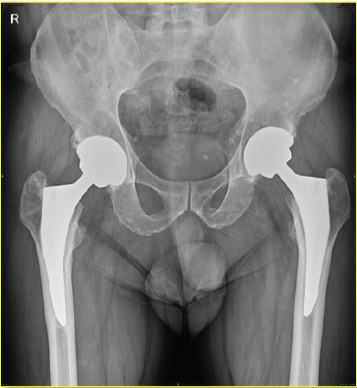

Case report: This case study relates the history of a 56-year-old man with ankylosing spondylitis who underwent bilateral THA using a CoC articulations. Initially asymptomatic for 4 years, he developed pain, swelling around the right hip, and his imaging showed extensive osteolysis with pseudotumor formation. His fine-needle aspiration cytology report was inconclusive, so he underwent stage 1 procedure that is removal of prosthesis and biopsy. His histopathology report confirmed pseudotumor formation with presence of fibrin, proliferating fibroblasts, hemosiderin-laden macrophages and lymphocytes. Since the patient was not keen on second stage revision arthroplasty, he was mobilized with heel and sole raise and walking aid.

Conclusion: Pseudotumor formation occurred without any damage to ceramic head and liner, without any malposition of components, with no impingement between components and normal metal ion levels in our case. This case report further strengthen existing literature about pseudotumor formation in CoC articulation. Further studies needed to know exact tribology and individual immune response for ceramic wear debris.